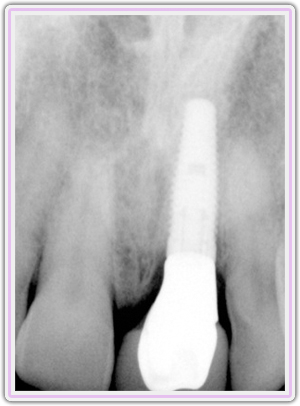

Pre-op X-Ray Showing The Fracture

X-Ray Showing The Custom Abutment In Place

Final X-Ray Showing Implant